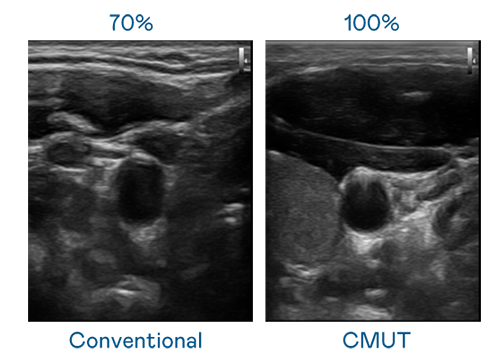

CMUT 技术是一种用电容式微机电元件来产生超音波讯号的技术。与传统 PZT 压电式技术相比,CMUT 频宽增加 30%,更宽频的超音波讯号让影像解析度大幅提升,是实现高影像品质医疗超音波扫描、促进精准医疗发展的关键技术。

大频宽带来超清晰影像

超音波影像的解析度高低,首先取决于探头能发出的讯号频宽。17.C18-起草免费 CMUT 可提供高清晰的超音波讯号,提供高频宽、高灵敏度、影像纹理细节更高的超音波影像,协助医护人员缩短影像判读时间及利用精准的医疗影像进行诊断。